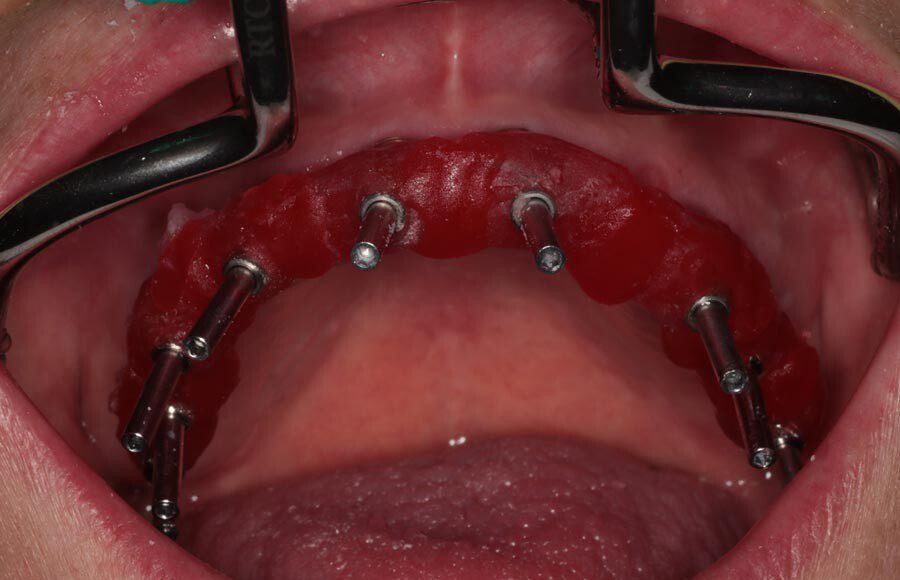

Teeth were removed and dental implants were placed. Because the bone was dense and the implants could be inserted with good primary stability, we were able to make impressions and load the implants that day.

Teeth were removed and dental implants were placed. Because the bone was dense and the implants could be inserted with good primary stability, we were able to make impressions and load the implants that day.